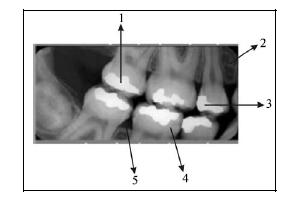

Assinale a opção incorreta, tendo como referência a figura acima.